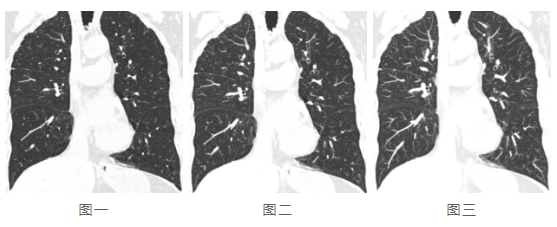

再看(kan)下(xia)面三張圖:

22.png

三張圖的(de)層厚(hou)分別為(wei)0.5mm、2mm、5mm,隨著層厚(hou)的(de)增加,病灶因重疊(die)而被忽(hu)略的(de)可(ke)能性(xing)同步(bu)增加。因此(ci),對于發現細小病灶如肺小結節,層厚調節顯然是必備的工具。